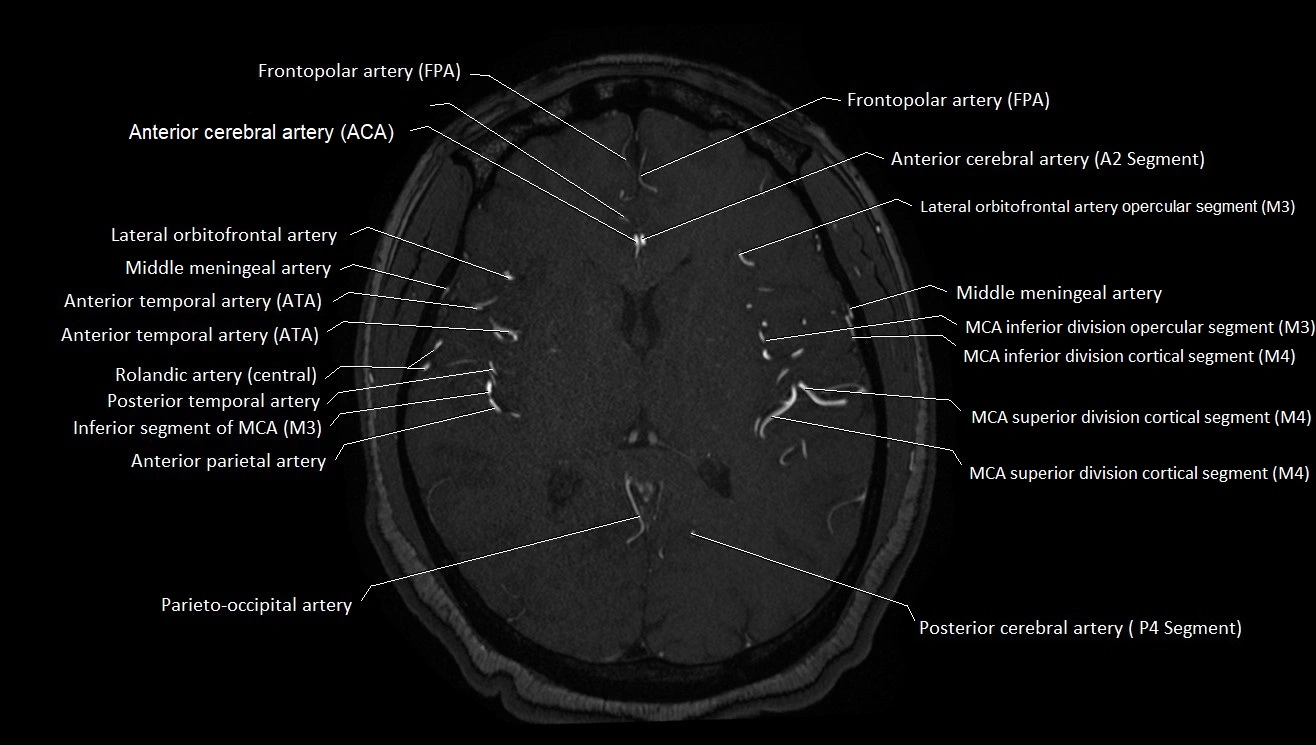

MRA (Magnetic Resonance Angiography):

• Flow-related enhancement makes the AChA appear as a bright, linear vascular signal against suppressed background

• High sensitivity for origin and proximal course; distal branches may be too small to resolve

• Detects stenosis, occlusion, aneurysm, AVM feeders

MRI images

image